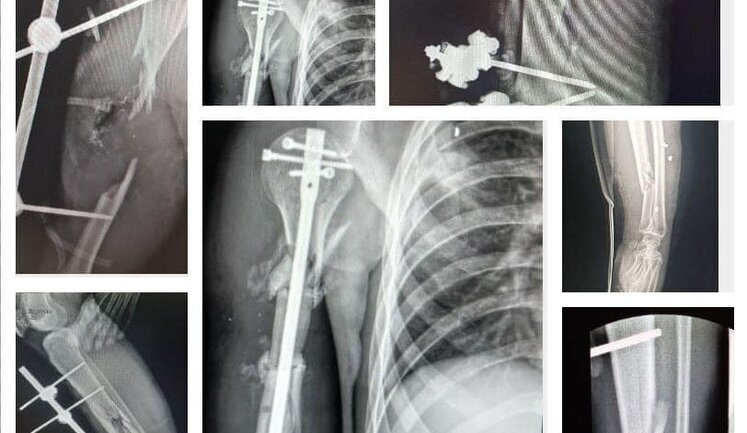

Благотворительный проект "На Шапку": украинские музыканты собрали деньги на 153 костных импланта для раненых военных, - радиоведущая Сотник. ФОТО С помощью благотворительного проекта "На Шапку" украинские музыканты собрали деньги на 153 костных импланта для раненых военных. 1 871 1 Ранее в тренде: Война